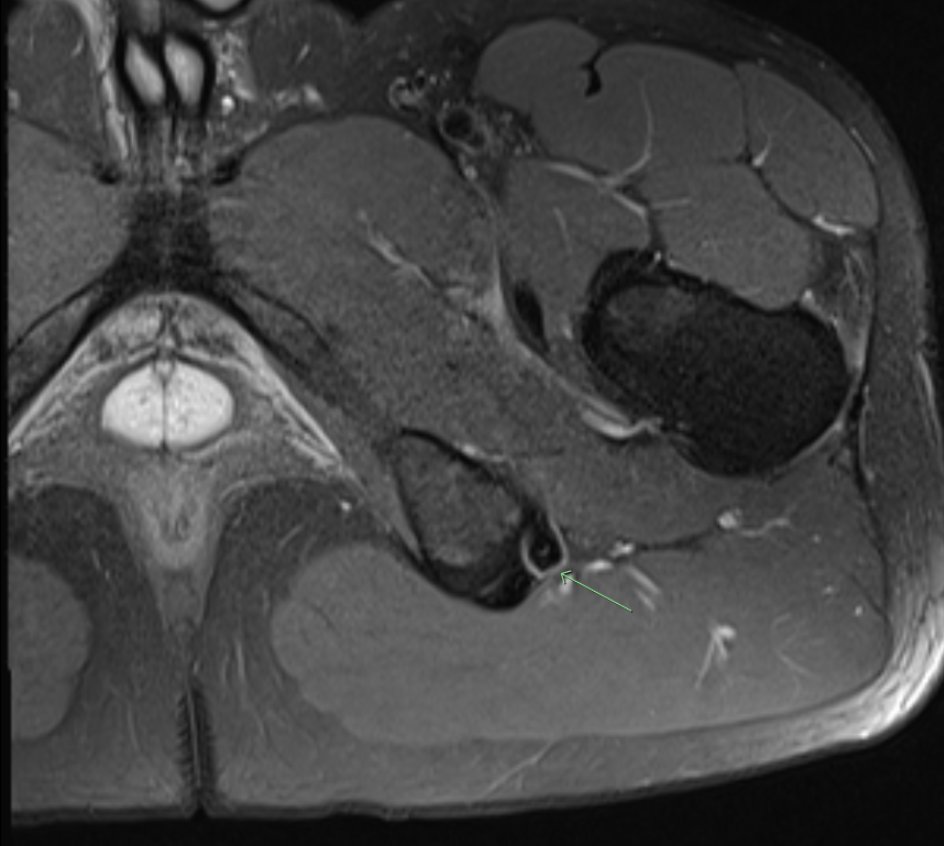

Use the ‘Dropped ice cream sign’ to identify proximal hamstring tendon avulsion on MRI:

▶️Tuberosity=Cone

▶️Tendons=Scoops, CaraMEl (Conjoint MEdial) & StracciatelLA (Semimembranosus LAteral)